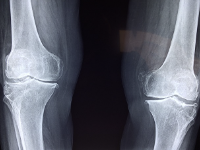

무릎 관절염은 단순 방사선 촬영 검사로 진단할 수 있으며, 관절 간격의 좁아짐과 골극 형성 등을 기준으로 초기/중기/말기 단계로 구분할 수 있습니다.